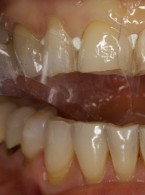

• Zastosowanie kompozytów w bezpośredniej odbudowie zębów przednich po urazie

• Bezpośrednia licówka kompozytowa w odcinku przednim wykonana z użyciem uniwersalnego kompozytu typu…